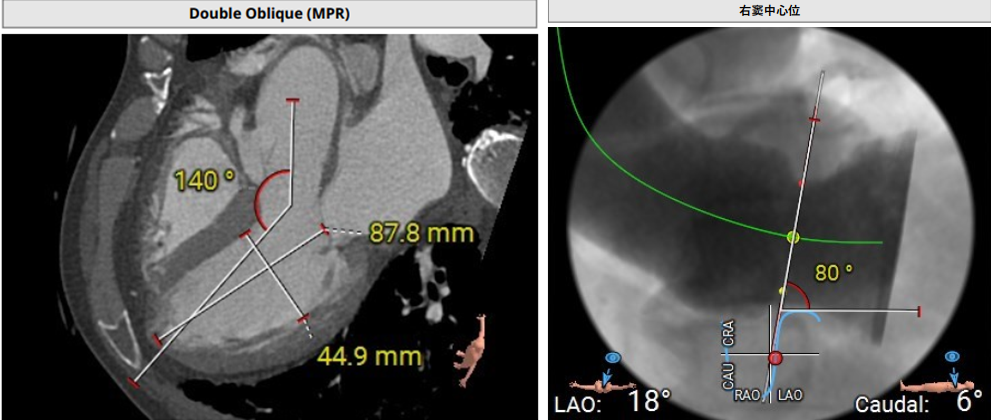

术前评估

术前影像评估提示,患者主动脉为TYPE0型二叶瓣,瓣叶增厚,边界显示不清,疑似瓣叶脱垂,少量钙化。主动脉瓣环直径31.5mm,左心室流出道直径35.3mm,STJ直径32.3mm,升主动脉直径37.3mm,冠脉开口高度充足(左冠15.6mm,右冠19.1 mm),左室与主动脉夹角158°。

上下滑动查看更多照片

该患者心脏结构对于手术存在一定挑战,主要在于患者为主动脉TYPE0型二叶瓣,左右冠同窦,瓣窦部扩张,窦部最大径线42.7mm,最终手术团队根据患者解剖结构,将两枚夹持件放入同一窦内,第三枚夹持件放置在无窦内。此外,患者同种异体原位肝移植术后2年,长期服用抗排斥药物,行传统体外循环下的心脏手术风险较高。

瓣膜选型:JS/TAVI-33瓣膜

术中回顾及效果

在DSA与超声引导下,手术团队高效精准地完成了瓣膜的定位、释放与功能评估。手术过程顺利,夹持件入窦与定位一气呵成,三枚夹持件的释放与锚定位置与术前评估完全一致,器械用时仅6min左右。患者主动脉瓣重度反流纠正,术后无反流、无瓣周漏。术后心脏彩超显示人工生物瓣启闭良好,平均跨瓣压差3mmHg,流速正常,舒张压从30mmHg提升至70mmHg。